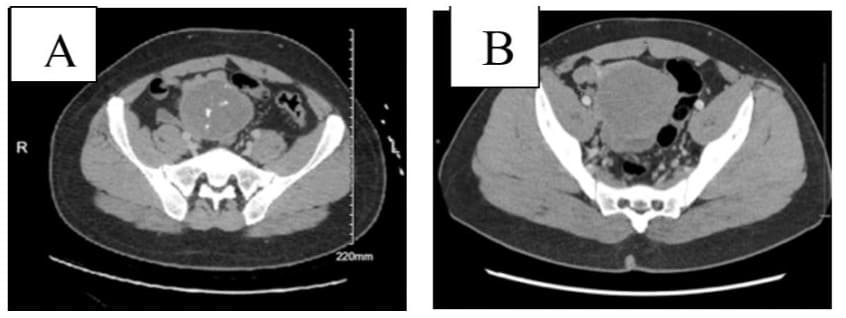

Paternal aunt: breast cancer

Figure 1: Contrast-enhanced computed tomography of the abdomen and pelvis (06/2024) of a 32-year-old-man with anemia, showing (A) a slight decrease of the complex mesenteric mass from maximum 8.2 cm diameter to 7.8 cm diameter, and (B) CT scan a year ago (01/2023) showed large complex heterogenous mass superior to the bladder and between the bladder and the bowel measuring 8.5 x 6.7 x 7.6 cm.